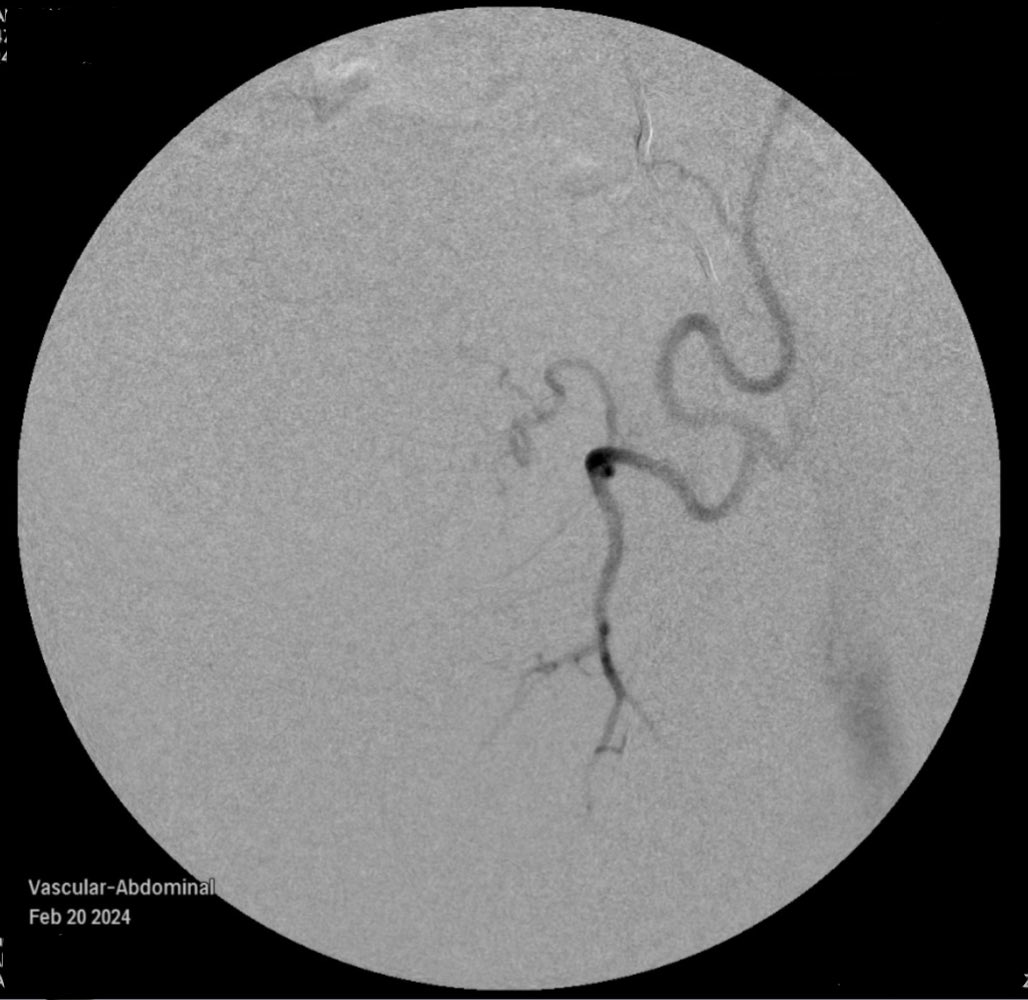

We have upcoming session on VIRshadowing.com starting April! 🥼: David Mittelstein, MD, PhD @drmittelstein Cases: 4/28: Retroperitoneal Cystic Mass Embo 5/12: Fractured Port Cath Retrieval 6/9: Post-Partum Uterine Bleeding Register early! @WCVISociety @SIRRFS